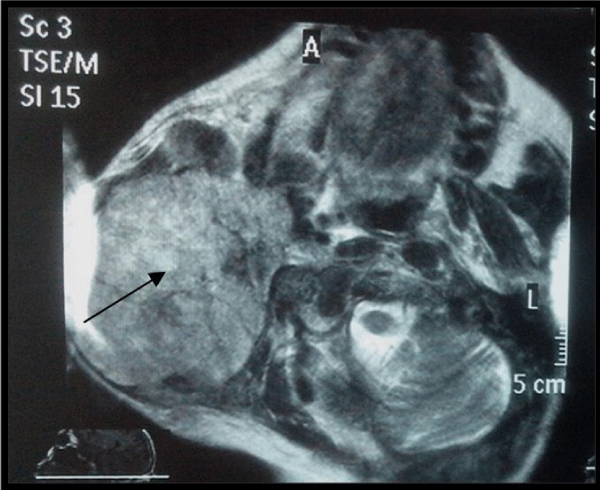

Out of 200 patients, there were 170 males and 30 females. Mean age of male and female patients was 40.27±15.04 and 40.12±12.15 years respectively. Youngest patient age was 10 years for male and 15 years for female, but the eldest patient age was same for both the genders i.e. 80 years. Based on MRI imaging characteristics 125 patients were labelled as having benign and 75 as having malignant tumours (Figure-1), while histopathological findings diagnosed 121 parotid tumours as benign and 79 as malignant tumours (Figure-2). On both the modalities i.e. on MRI and Histopathology, 113 patients were diagnosed as benign and 67 patients as having malignant parotid gland tumours (Image 1). Total of 20 patients had contradictory results, out of them 12 patients were diagnosed as benign on MRI but they were malignant on histopathology. Similarly 8 patients were diagnosed as having malignant tumour on MRI but on histopathology they were found to be having benign features (Table 1). Sensitivity, specificity, positive and negative predictive value of MRI was 90.4%, 89.33%, 93.39% and 84.41% respectively. The overall diagnostic accuracy of MRI was found to be 90% while taking results of histopathology as a gold standard.

False-positive diagnoses, in detecting the presence of malignant parotid tumour could result in more radical surgery involving more risk to the patient who might not actually require lymph node dissection. So preoperative assessment is helpful in avoiding aggressive surgical plan as well as unnecessary surgery of inflammatory disease and possible risk to facial nerve injury [13]. In our study, 8 false positive diagnoses were made on the basis of MRI findings. Bulky mass (more than 5 cm) with compressive behaviour and/or cystic lesion were interpreted as suspicious on MRI which turned up as inflammatory lesions, cystic pleomorphic adenomas and Warthin tumours on histopathology. These errors were probably due to the large size of the tumour leading to the misinterpretation of its relation to adjacent structures and necrosis.